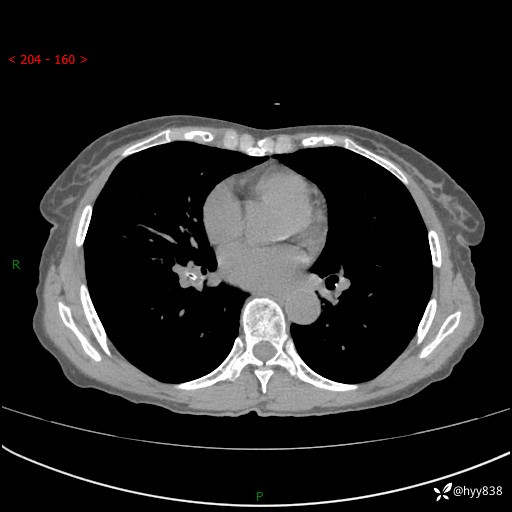

患者性别:男

患者年龄:69岁

简要病史:咳嗽咳痰2月,夜间加重

临床诊断:感染

胸部CT平扫